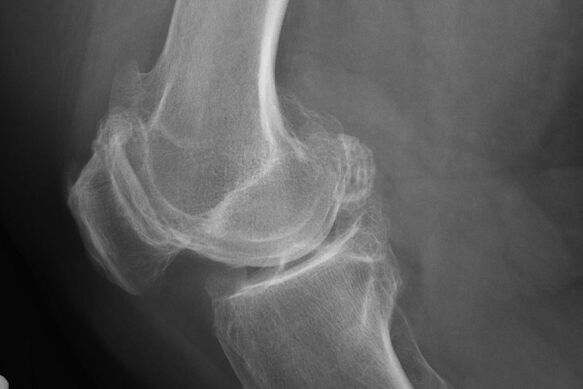

كقاعدة عامة ، يحدث تشخيص المرض في هذه المرحلة عن طريق الصدفة ، أثناء X -Ray. على ذلك ، قد يلاحظ الطبيب بعض المخالفات على الغضروف. من الممكن أيضًا تضييق التجويف بين أجزاء المفصل.

سوف تساعد X -Ray في تحديد الانحرافات في الغضروف.

بعد الفحص ، يصف الطبيب التصوير الشعاعي للمريض. هذه هي الطريقة الرئيسية لتشخيص التهاب المفاصل لمفصل الركبة من أي درجة.

X -Ray يعطي الطبيب فكرة عن التغييرات التي تحدث في غضروف المفصل. ومع ذلك ، في بعض الحالات ، لا يمكن تحديد المرحلة الأولية في الصورة.

إذا لزم الأمر ، قد يصف الطبيب مرورًا متكررًا من التصوير المقطعي بالأشعة السينية أو التصوير بالرنين المغناطيسي.